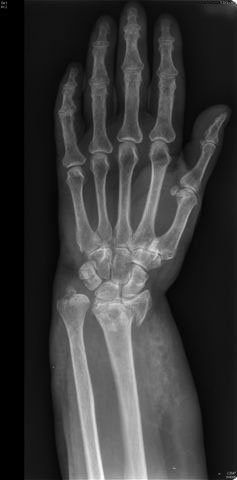

Carpo normal

ACT Alteraciones degenerativas en muñeca.